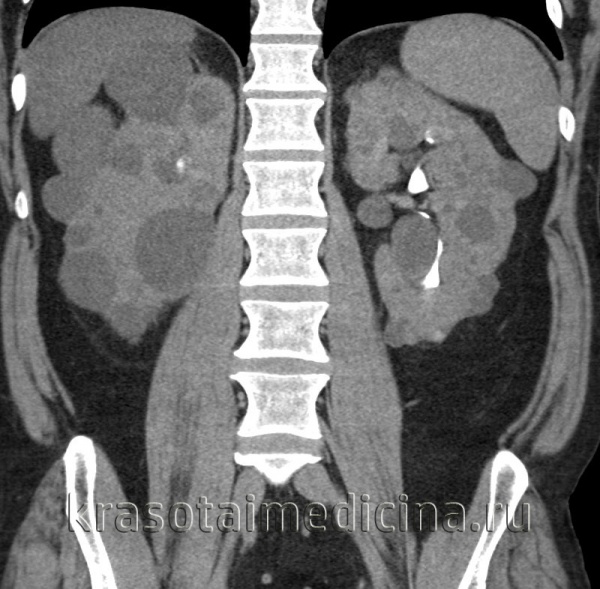

Рисунок 5,6, КТ-изображение в корональной проекции, поликистоз почек, кисты печени, поджелудочной железы.

• Множественные билатеральные кисты в увеличенных почках:

о Осложненные кисты:

- Геморрагические кисты: гиперденсное содержимое (60-90 HU), возможны пристеночные кальцификаты

(Слева) КТ без контрастирования, аксиальная проекция: поликистозное поражение почек и печени. В то время как большинство кист почки гиподенсные, периферические кисты левой почки - гиперденсные, сравнимые по плотности с геморрагическими кистами.

(Слева) КТ с контрастированием у пациента с аутосомно-доминантной поликистозной болезнью почек, аксиальная проекция: множественные двусторонние простые кисты почек. Стенки кист плохо различимы, не накапливают контраст.

(Справа) УЗИ, продольная плоскость сканирования: у этого же пациента обнаружены множественные простые анэхогенные кисты в увеличенной правой почке. Для данного заболевания характерно прогрессирующее увеличение объема кист и почки.г) Патология: